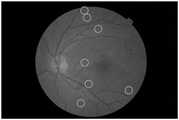

FIG. 5 is a schematic structural diagram of an attention-guiding filter in the detection method of the present invention.

s6, adopting the retinal microaneurysm recognition model obtained in the step S5 to recognize and detect the real-time obtained retinal color fundus image so as to finish automatic detection of the retinal microaneurysm; the results of the detection are shown in FIG. 6.

s6, adopting the retinal microaneurysm recognition model obtained in the step S5 to recognize and detect the real-time obtained retinal color fundus image so as to finish automatic detection of the retinal microaneurysm; the detection results are shown in FIG. 6;

The imaging method of the invention can be directly applied to equipment for imaging fundus images, the equipment adopts the method of the invention to detect and identify the microaneurysms after imaging and acquiring corresponding fundus images each time, and according to the detection and identification results, corresponding imaging and marking operations (such as marking, circling and the like operations on the microaneurysms) can be carried out on the fundus images again.